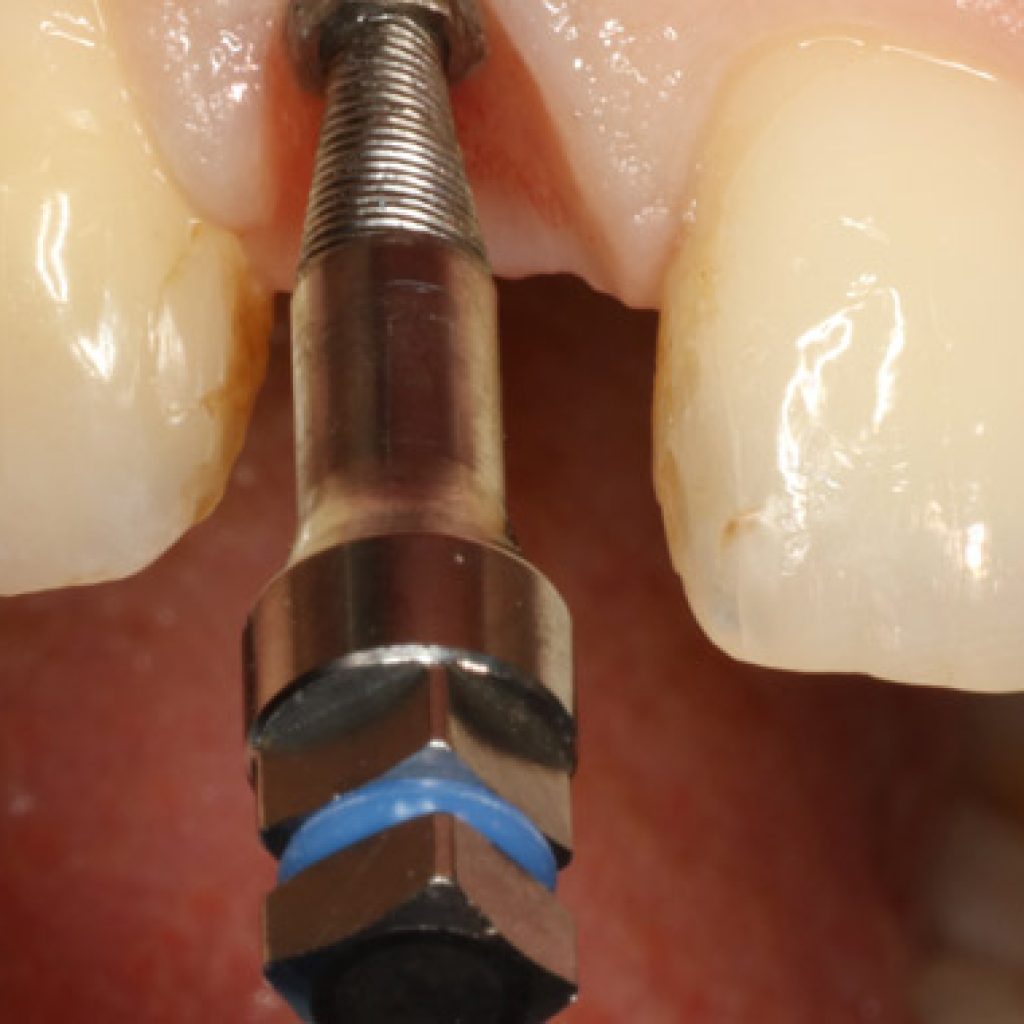

En la sociedad moderna la estética de la sonrisa está confirmanda como una preocupación muy importante en cuanto a las relaciones interpersonales, y representa un punto clave durante el proceso de toma de decisiones en pacientes que requieren rehabilitación oral compleja y combinada. Los datos de la literatura muestran que las personas atractivas son juzgadas […]